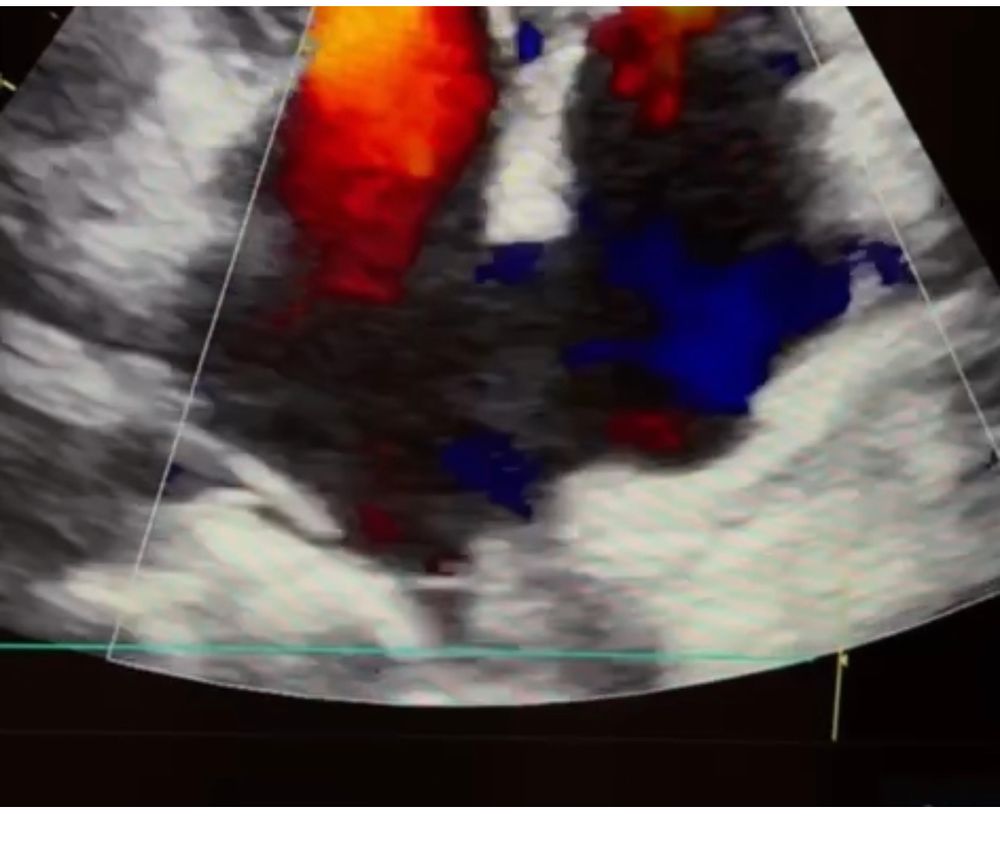

💚Эхо-кг ( узи сердца)